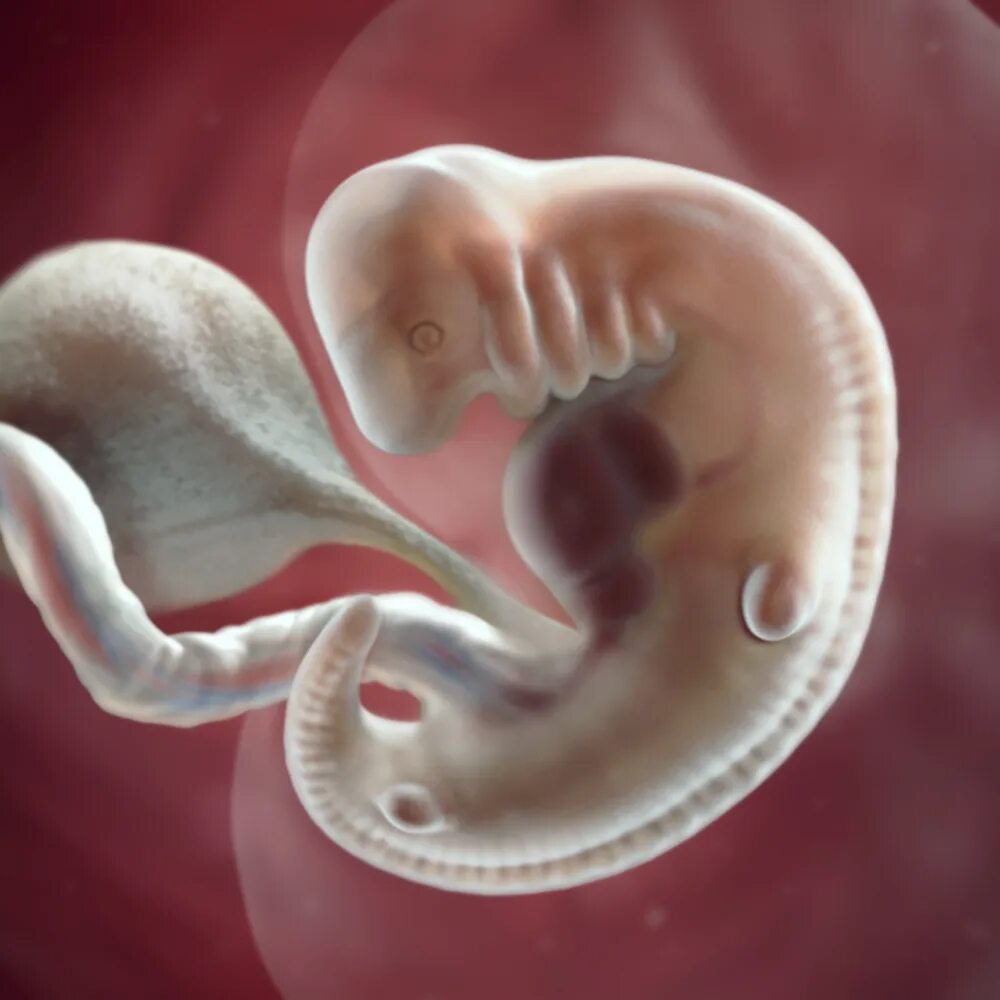

6 недель беременности как выглядит эмбрион